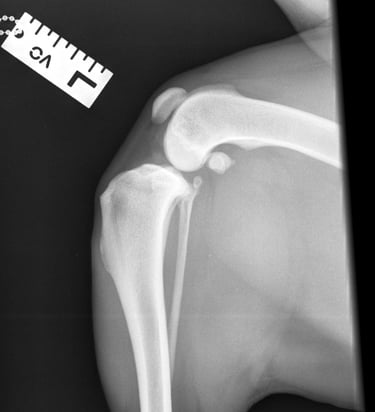

Orthogonal radiographs revealed findings consistent with cranial cruciate ligament disease. The lateral view of the affected limb (Fig. 2) shows joint effusion along with degenerative changes suggestive of osteoarthritis affecting the distal pole of the patella, proximal trochlear groove, and fabellae. The contralateral (left) stifle (Fig. 1) appears normal and serves as a reference. A cranial drawer test was performed under sedation and yielded a positive result.

Fig. 2